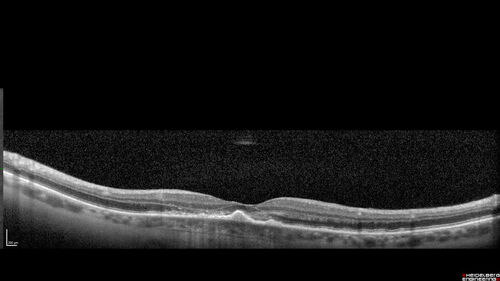

Macular Serpiginous Chorioretinopathy

75 year old vision with central placoid lesions. She tested negative for TB and Syphilis. The final visual acuity in both eyes was 1/200.